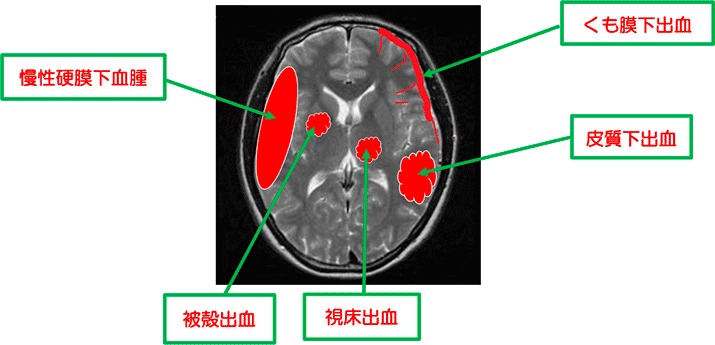

5. 脳出血による血管性認知症

脳出血の病態

- ① 高血圧性脳出血⇒視床出血、被殻出血

- ② くも膜下出血(脳動脈瘤破裂、脳動静脈奇形破裂...など)

- ③ アミロイド血管症による皮質下出血

- ④ 頭部外傷に起因する慢性硬膜下血種